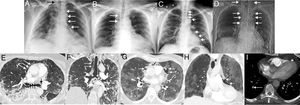

Una vez ingresados, se inició el tratamiento de la infección por SARS-CoV-2 y se emplearon otros fármacos (antitérmicos, broncodilatadores, corticoides…) en función de las necesidades particulares de cada paciente. Los cuatro pacientes requirieron a lo largo de su ingreso (antes de la aparición del NE) administración de oxígeno a través de gafas nasales o mascarillas (simples o con reservorio), pero no necesitaron ventilación mecánica. Ninguno de los cuatro pacientes tenía antecedentes de tabaquismo y en ningún caso había historia previa de neumotórax, NE o de enfermedades pulmonares. Durante el ingreso los cuatro pacientes desarrollaron como complicación un NE (no relacionado con procedimientos invasivos como una intubación traqueal o una traqueotomía), no sospechado clínicamente en ningún caso, y detectado inicialmente mediante radiografía de tórax en tres de ellos y mediante tomografía computarizada (TC) en un caso en el que se sospechó un tromboembolismo pulmonar. En las radiografías de tórax se identificó la presencia de gas ectópico disecando los tejidos del mediastino y del cuello (fig. 1A-D). En uno de los pacientes estudiados con TC se observaron consolidaciones, bronquiectasias de tracción y la presencia de gas disecando el mediastino, incluyendo las paredes de ambos bronquios principales (fig. 1E-F). En otro paciente estudiado mediante TC se identificaron extensas opacidades en empedrado (asociación de opacidades de atenuación en vidrio deslustrado y de engrosamiento del intersticio pulmonar) y una pequeña cantidad de gas en la grasa prevascular del mediastino (fig. 1G-H). La evolución clínica fue favorable en tres de los cuatro casos; una paciente falleció por complicaciones infecciosas no relacionadas con el NE (neumonía por Pseudomonas aeruginosa y bacteriemia por esta bacteria y por Enterococcus faecalis). Uno de los casos de evolución favorable fue diagnosticado de un tromboembolismo pulmonar mediante angio-TC de tórax (fig. 1I). Ningún NE requirió tratamiento quirúrgico y los cuatro casos se manejaron conservadoramente, con desaparición del NE en controles radiológicos. La tabla 1 resume los aspectos clínicos más importantes de los cuatro pacientes con NE.

A) Radiografía de tórax posteroanterior en mujer de 60 años ingresada con neumonía bilateral por SARS-CoV-2 en la que se observa un neumomediastino incidental (flechas blancas). Obsérvese la extensión del gas a los tejidos blandos del cuello (flecha negra). B) Radiografía de tórax posteroanterior en varón de 62 años ingresado con neumonía bilateral por SARS-CoV-2, que presentó dolor torácico y disnea. En la radiografía se observa un neumomediastino paratraqueal derecho (flechas). C) Radiografía de tórax posteroanterior en varón de 58 años con neumonía bilateral por SARS-CoV-2, que presentó un episodio de dolor torácico e hipotensión. En la radiografía se observa un neumomediastino con neumopericardio (flecha) y gas en los tejidos blandos de la región supraclavicular derecha (asteriscos). D) Topograma (correspondiente a una TC de tórax) del único neumomediastino diagnosticado mediante TC en una mujer de 64 años con neumonía bilateral por SARS-CoV-2, que presentó dolor torácico y disnea. En el topograma se observa un extenso neumomediastino con extensión a las partes blandas del cuello (flechas). E) Imagen axial de TC de tórax (ventana de pulmón) de la paciente de la imagen D que confirma la presencia de gas ectópico rodeando los bronquios principales (flechas negras) y disecando el pericardio (flechas blancas). F) Imagen coronal de TC de tórax (ventana de pulmón) de la paciente de la imagen D) en la que se puede apreciar aire disecando ambos bronquios principales (flechas cortas) y el tejido graso paratraqueal derecho (flechas largas). G) Imagen axial de TC de tórax (ventana de pulmón) del paciente de la imagen B que confirma la presencia de gas disecando el pericardio (flechas). H) Imagen coronal de TC de tórax (ventana de pulmón) del paciente de la imagen B que muestra el gas disecando el pericardio (flechas). I) Imagen axial de TC de tórax (ventana de mediastino) del paciente de la imagen B en la que se identifica un defecto de repleción en una arteria subsegmentaria del lóbulo inferior derecho (flecha larga). Obsérvese la presencia de gas en la grasa pericárdica (flecha corta).